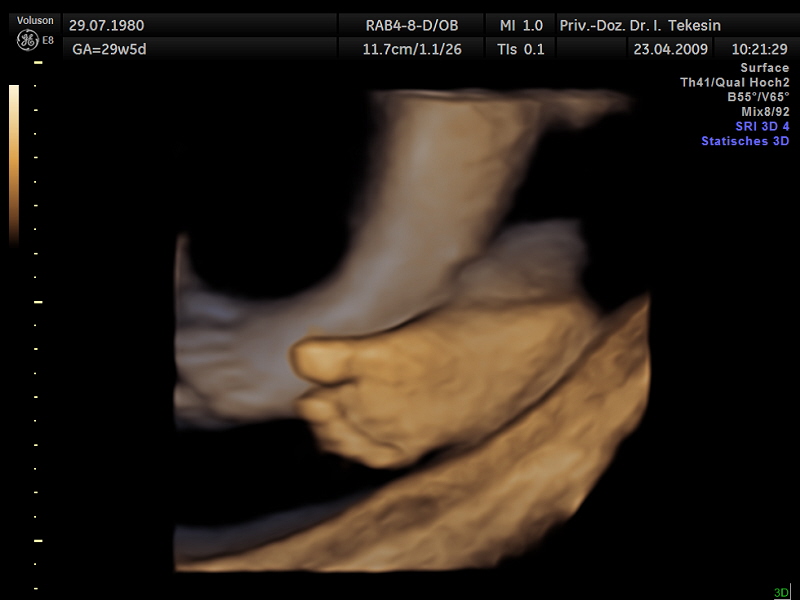

Ein Fuß

Ein Fuß (3D-Darstellung)